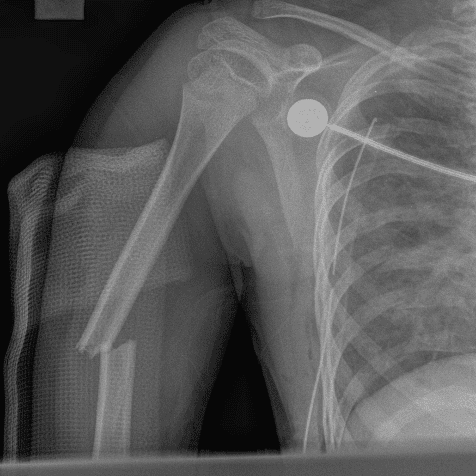

Simuliert den Dienst durch subtile oder schwierige Fälle und einige Normalbefunde.

30 Fälle